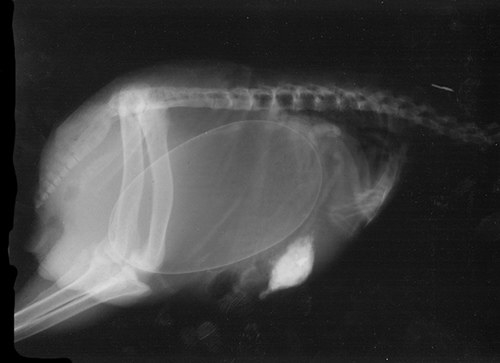

Беременная черепаха.